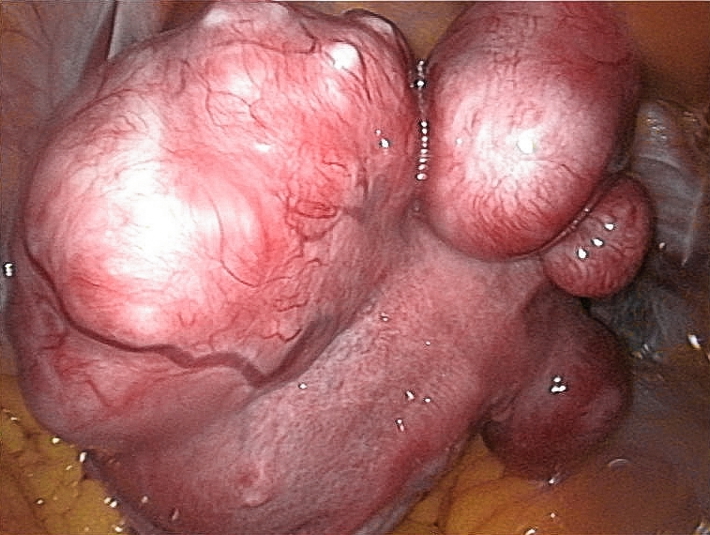

Macroscopic

- Round, well-circumscribed, white/tan solid nodules

- Range in size from microscopic to massive (e.g. grapefruit-sized)

- Typically multiple fibroids present